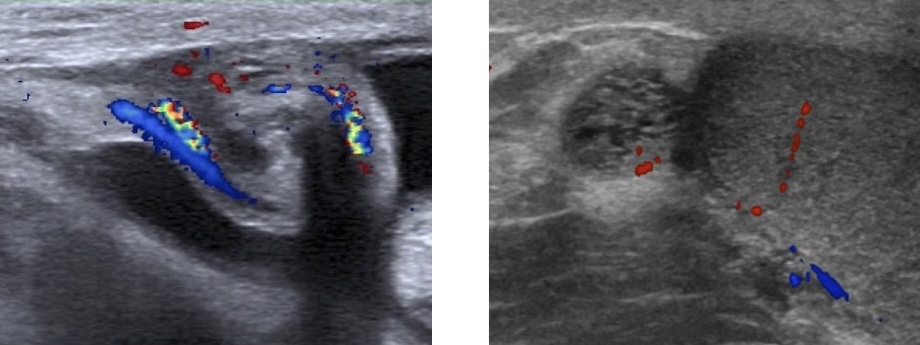

- non compressible, > 6 mm (TDM > 7 mm), hyperhémie, hyperécho autour, 25% stercolithe

- contenu liquidien + ligne hyper (sous-muqueuse) + anneau hypo (musculeuse)

- complications : plastron, abcès, péritonite

- DD = mucocèle (mucoviscidose ++), hyperplasie lymphoïde (âge scolaire ++)

- DD d'exclusion = adénolymphite mésentérique (> 3 gg > 5 mm)